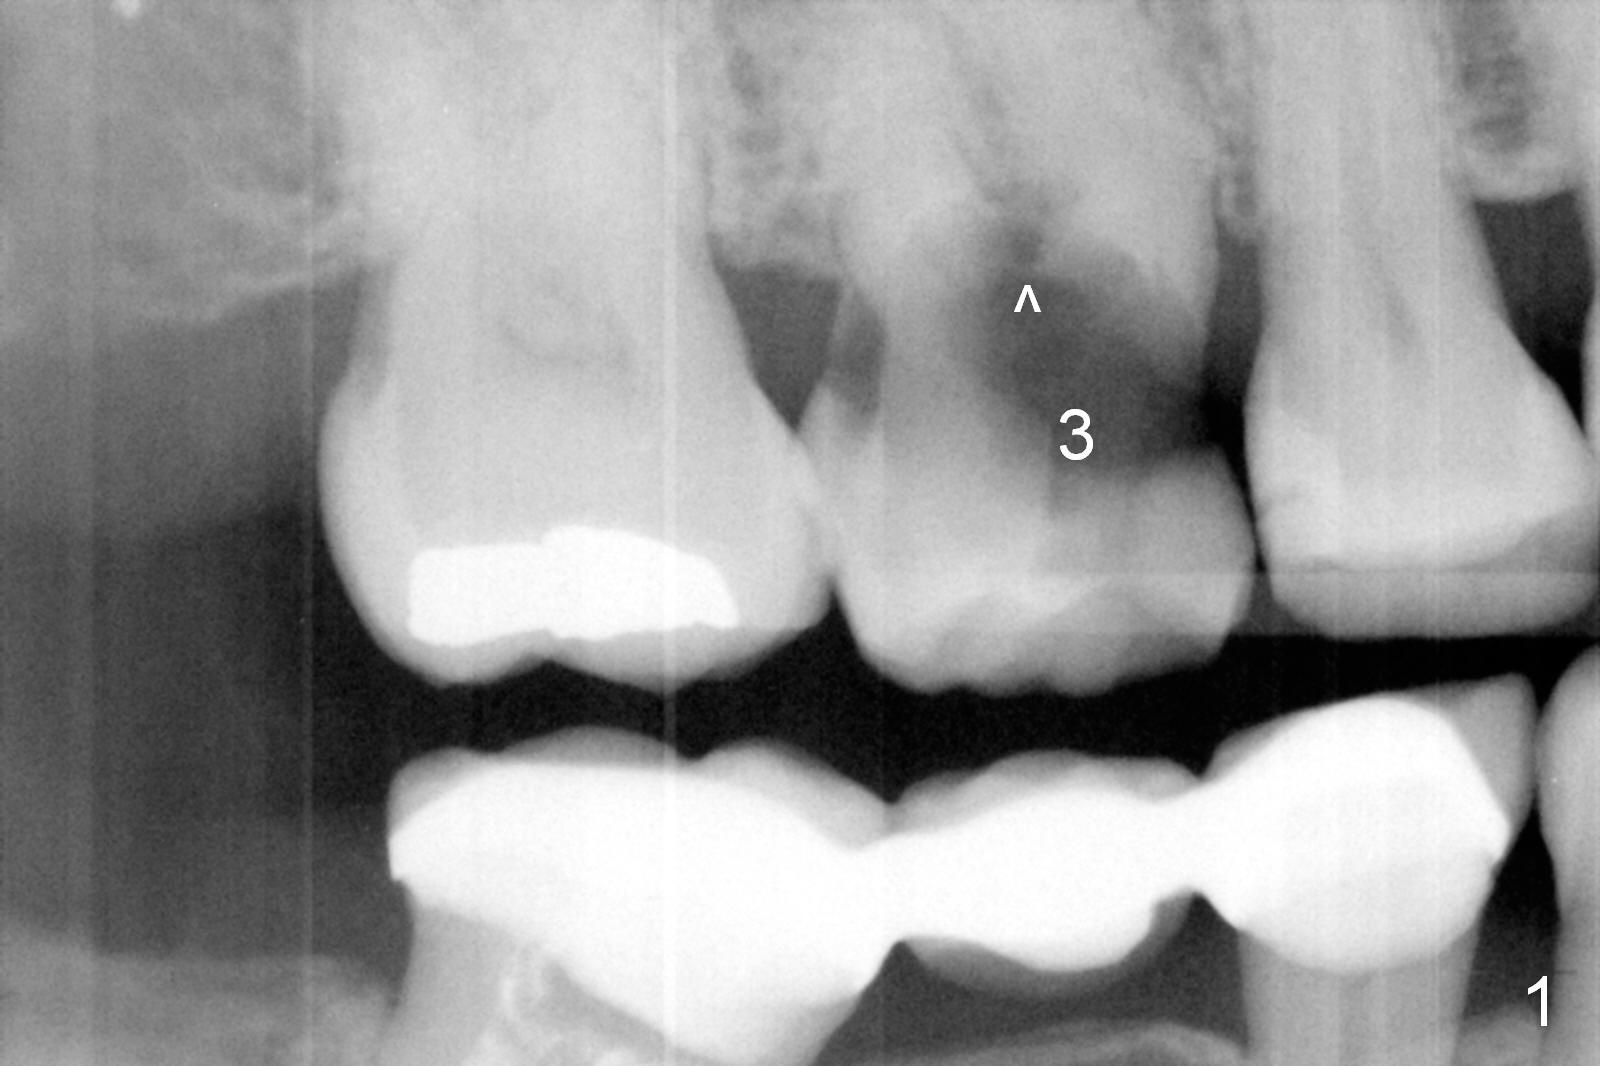

A 52-year-old woman is a dental phobic. Her main concern is the tooth #3 with caries apparently involving the furca (Fig.1 ^). Before extraction, take photos to show a polyp in the pulpal chamber, which is most likely periodontal. After extraction (prepare surgical handpiece, since the tooth most likely fractures at extraction), take photos to show furcal perforation, while the socket is packed with 3 pieces of gauze soaked with Metronidazole. There is apparently sufficient bone apical to the roots (Fig.2). To achieve primary stability, use an implant as long as possible (13 mm of IBS, Fig.3 (implant is drawn to be placed too superficial)) with large diameter appropriate to the septum. The plateau of the implant will be placed apical to the crests and coronal to the septum.